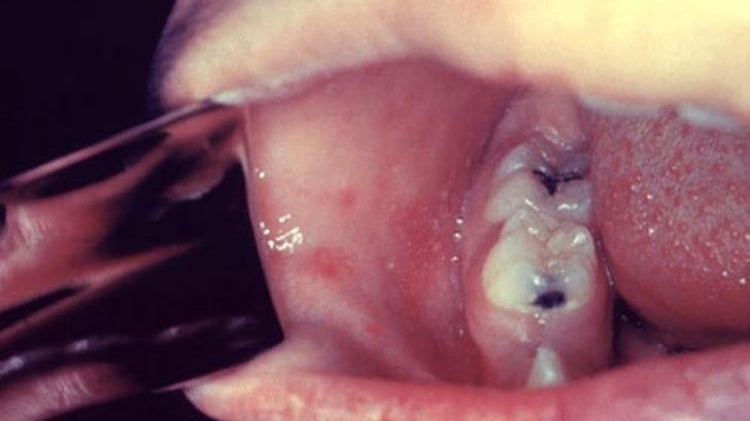

Đốm Koplik là các đốm trắng nhỏ xuất hiện trên niêm mạc má, đối diện răng hàm trên số 1–2, thường xuất hiện 2–3 ngày trước khi phát ban sởi. Đây là dấu hiệu đặc trưng, giúp nhận biết sớm bệnh sởi trước khi có triệu chứng ngoài da.

Hạt Koplik là một đặc trưng của bệnh sởi, đặc điểm nhận dạng hạt này đó là chúng thường có màu trắng hoặc hơi trắng như hạt cát, kích thước nhỏ như đầu đinh ghim. Chúng có thể xuất hiện từ vài nốt đến vài chục hay vài trăm nốt ngay tại niêm mạc má (phần phía trong miệng, ngang răng hàm).

Xung quanh các hạt Koplik ở niêm mạc má thường có sung huyết. Hạt này xuất hiện và biến mất nhanh chóng trong vòng khoảng từ 12 - 24 giờ.